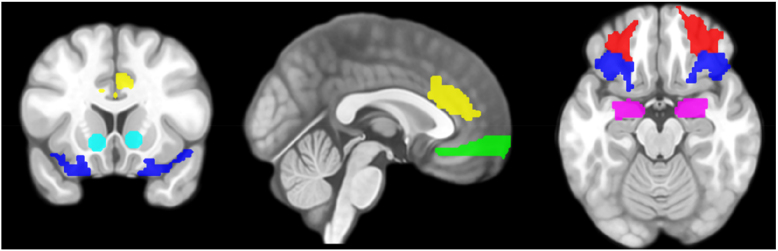

Results: In conditioning, subjective ratings increased, and reaction times were faster for both erotic and monetary cues among participants with CSB, along with altered activity in ventral striatum (vStr), dorsal anterior cingulate cortex (dACC), and anterior orbitofrontal cortex (aOFC). In extinction, self-assessment ratings remained elevated in the CSB group for both cues in a non-reward-specific fashion, accompanied by altered activity of dACC and vStr.